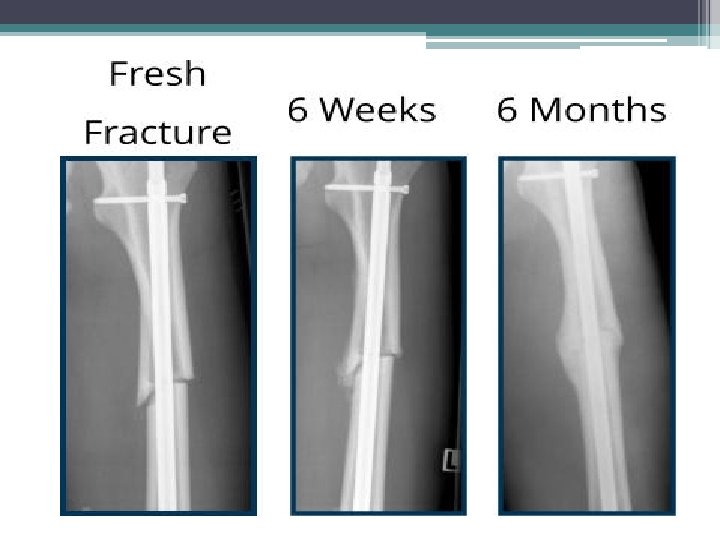

A) A 28 -year-old male presented femur shaft comminuted fracture and tibia shaft fracture. (B) He undertook closed reduction and internal fixation with intramedullary nail